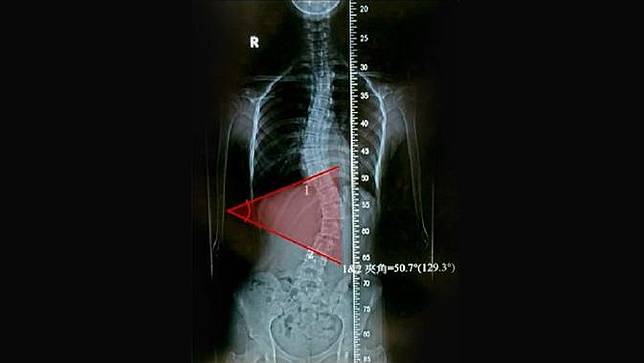

Gadis yang tak diketahui namanya itu mengalami perubahan sekitar 50 derajat pembengkokan tulang belakang dan mengalami kesakitan punggung yang cukup hebat. Kondisi tersebut yang membuat ibu dari gadis ini membawanya ke bagian ortopedi untuk diperiksa lebih lanjut.

Setelah diperiksa, diketahui bahwa pembengkokan tulang belakang yang cukup banyak ini berawal dari kebiasaan si gadis yang sering bermain smartphone dengan badan menyamping saat tidur.